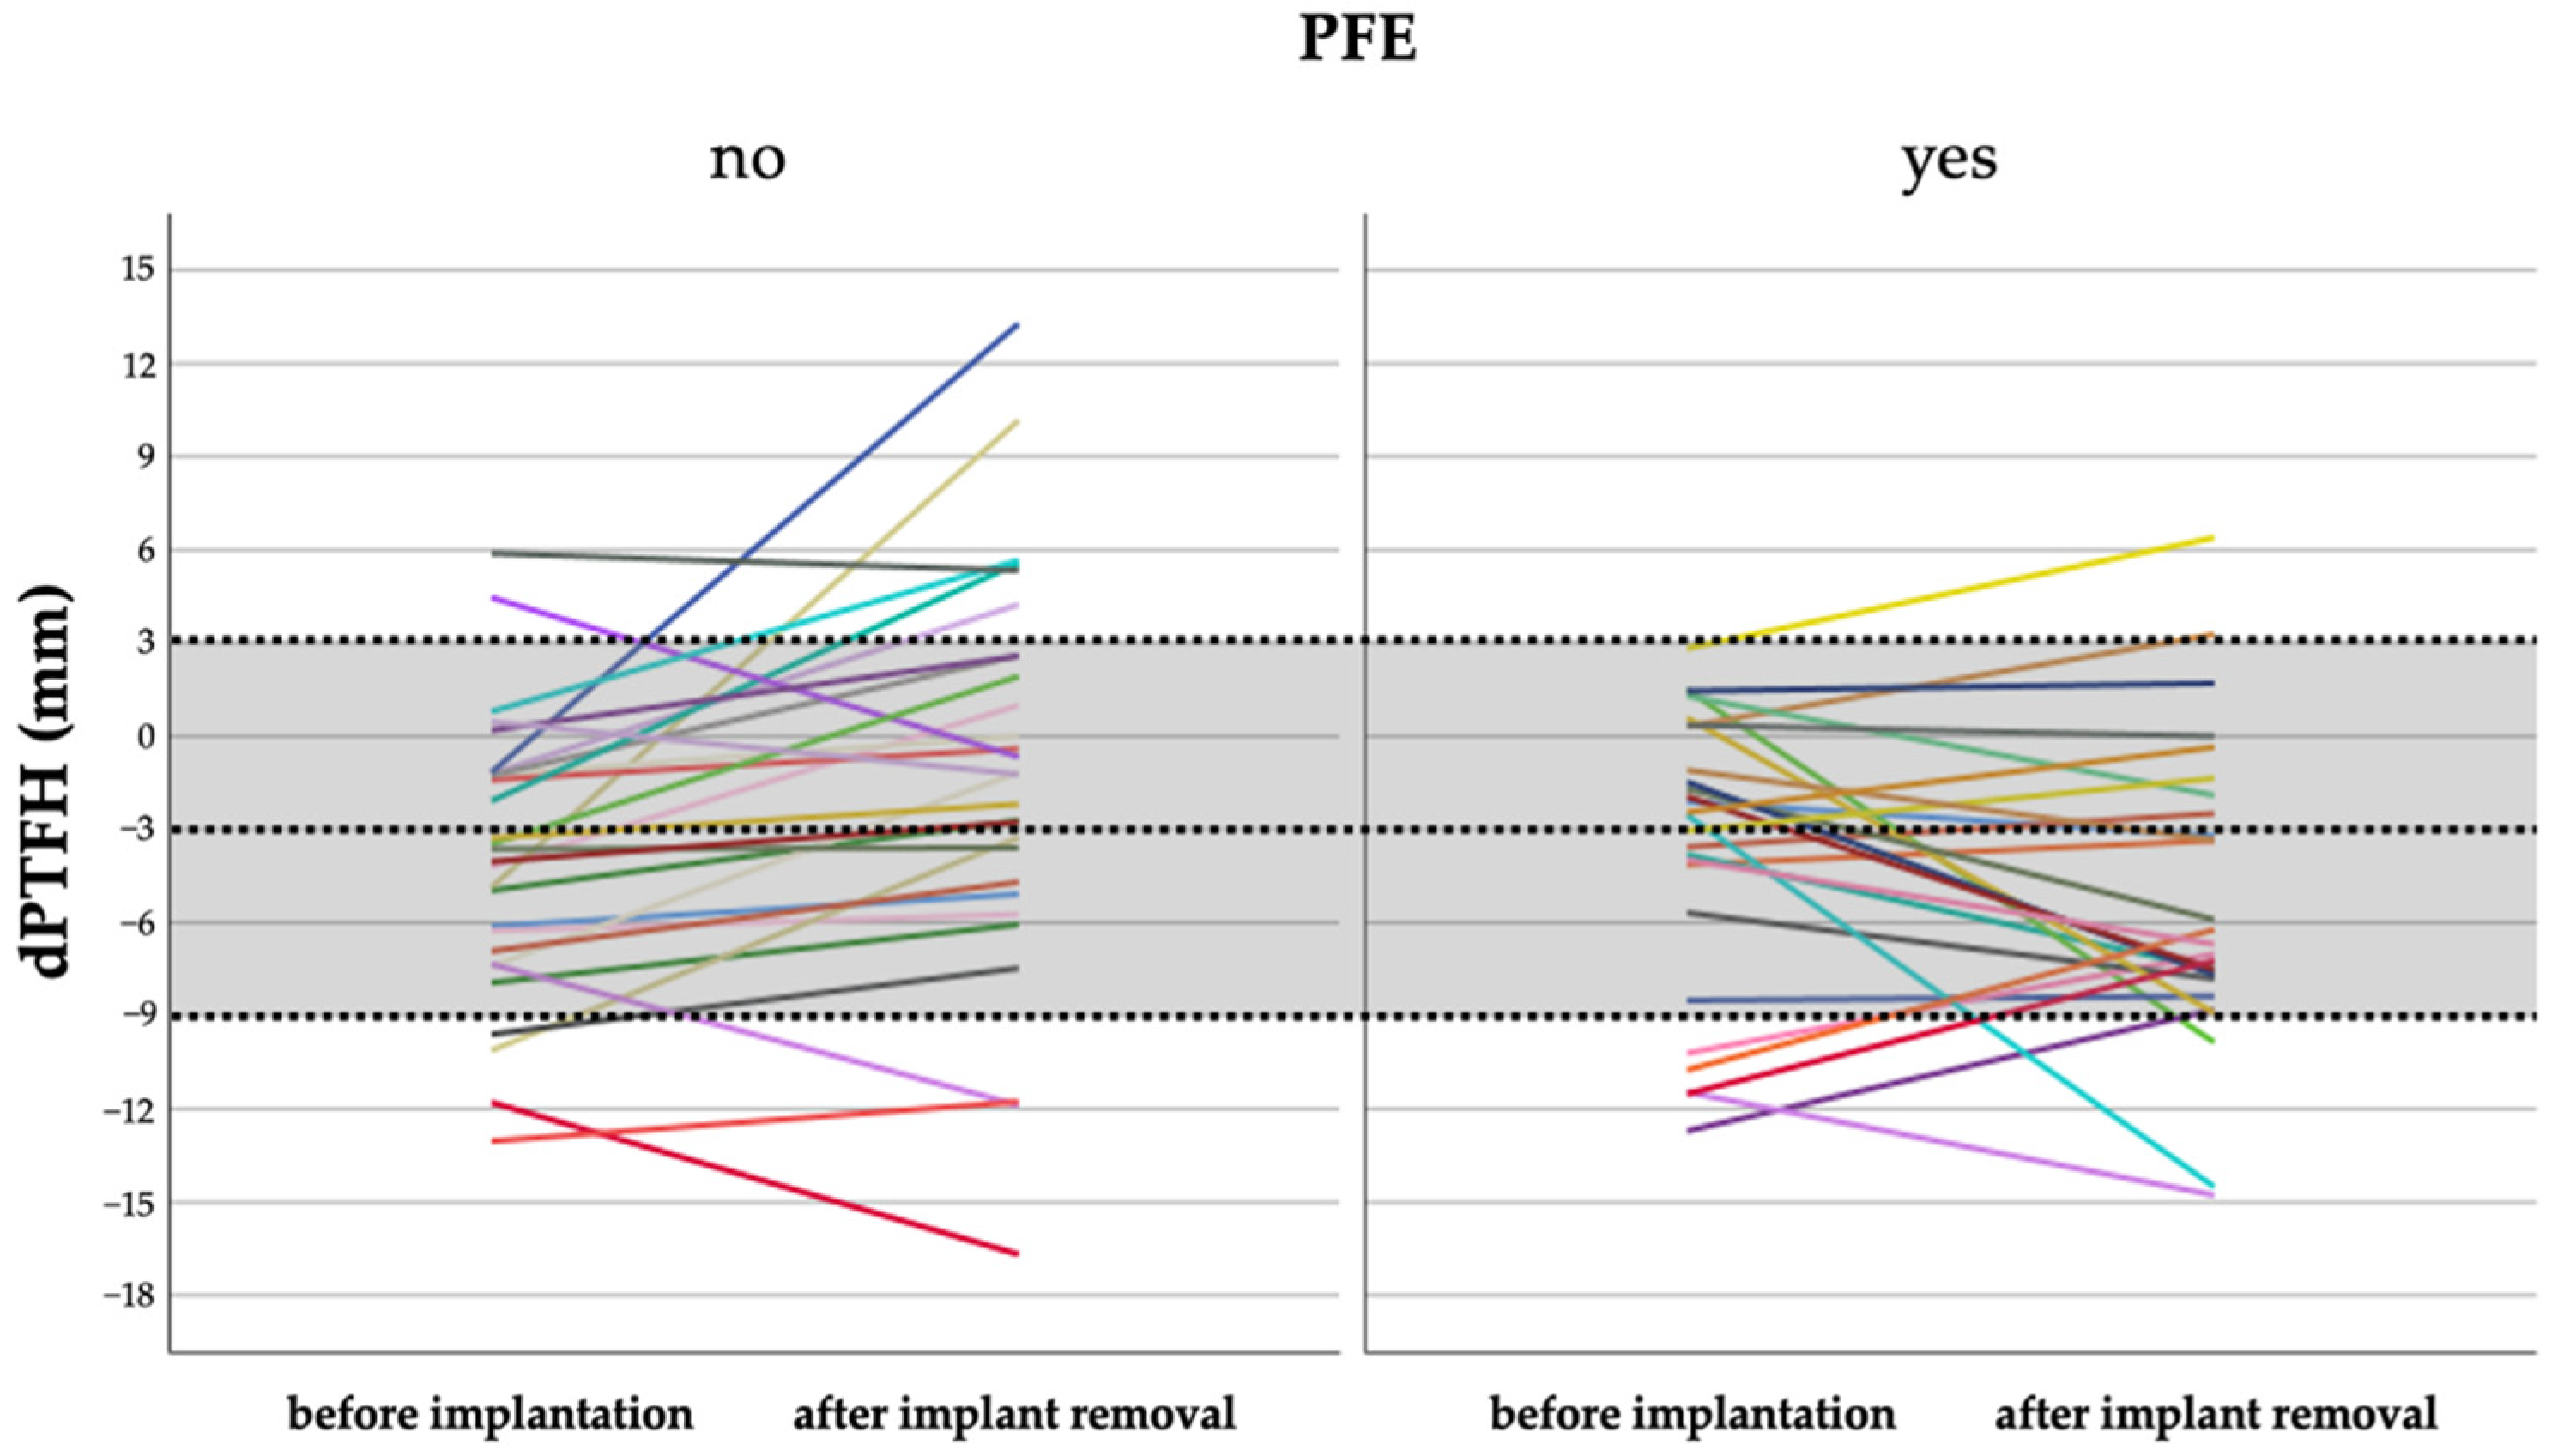

3.2. Radiographic Outcome Regarding Tibiofibular Relation

3.2.1. Comparison in Each of the Groups Treated with and without PFE

3.2.2. Comparison between the Groups Treated with and without PFE

| Distance proximal tibial physis to fibular head (mm; dPTFH) [16] | −3.4 (−12.7–3.5) | −5.1 (−14.8–6.4) | 0.223 | 3.7 (0.1–12) | −3.7 (−13.0–5.9) | −1.2 (−16.7–13.3) | 0.005 | 3.9 (0–15) | 0.876 |

| dPTFH within physiological range (%) | 21/27 (78) | 21/26 (81) | 1.000 | / | 25/31 (81) | 21/ 30 (70) | 0.508 | / | / |

| Distance proximal tibial physis to fibular head (dPTFH; mm) [16] | −3.4 (−12.7–3.5) | −3.7 (−13.0–5.9) | 0.546 | −5.1 (−14.8–6.4) | −1.2 (−16.7–13.3) | 0.018 |

| dPTFH within physiological range (%) | 77.8 | 80.6 | 1.000 | 80.8 | 70.0 | 0.508 |

| Group Treated with PFE (n = 27) | Group Treated without PFE (n = 31) | |||||

|---|---|---|---|---|---|---|

| Before Implantation | At Implant Removal | p-Value | Before Implantation | At Implant Removal | p-Value | |

| dPTFH out of physiological range [16] | 6/27 (22%) | 5/26 (19%) | 1.000 | 6/31 (19%) | 9/30 (30%) | 0.508 |

| Proximal fibular overgrowth | 1/27 (4%) | 2/26 (8%) | 0.500 | 2/31 (6%) | 6/30 (20%) | 0.219 |

| Newly developed overgrowth | / | 2/26 (8%) | / | / | 5/30 (17%) | / |

| Proximal fibular shortening | 5/27 (19%) | 3/26 (12%) | 0.687 | 4/31 (13%) | 3/30 (10%) | 1.000 |

| Newly developed shortening | / | 2/26 (8%) | / | / | 1 (3%) | / |